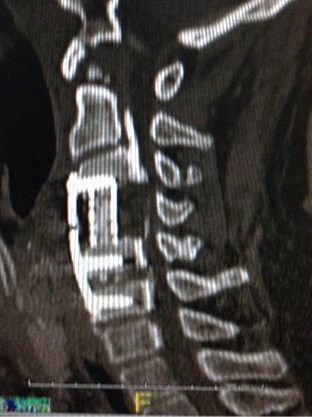

The first operation took place on the same week of Halloween. The plan was that the surgeons would cut open the front of my neck, remove the C4 bony segment of my cervical spine. Then they more or less scraped off some hardened material that was causing the compression. After which, they shored up the missing bony segment with a titanium cage and a screwed-on plate. The operation took about 15 hours or so. Though the doctors were optimistic, the verdict for a successful outcome was still in question. My wife and the lead surgeon stayed by my bedside at the ICU practically the whole night waiting for signs. Those signs came in the morning when after some poking, I indicated to them that I felt it. You can well imagine the audible sigh of relief in that room.